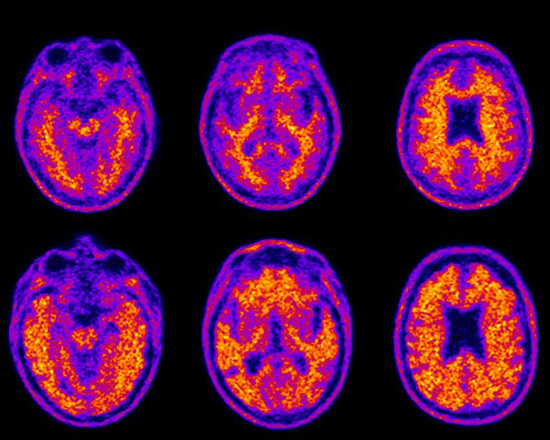

Aging adults often show signs of slowing when it comes to managing their finances, such as calculating their change when paying cash or balancing an account ledger. These changes happen even in adults who are cognitively healthy. But trouble managing money can also be a harbinger of dementia and, according to new Duke research in The Journal of Prevention of Alzheimer’s Disease, could be correlated to the amount of protein deposits built up in the brain. “There has been a misperception that financial difficulty may occur only in the late stages of dementia, but this can happen early and the changes can be subtle,” says P. Murali Doraiswamy, MBBS, a professor of psychiatry and geriatrics at Duke and senior author of the paper. “The more we can understand adults’ financial decision-making capacity and how that may change with aging, the better we can inform society about those issues.” The findings are based on 243 adults ages 55 to 90 participating in a longitudinal study called the Alzheimer’s Disease Neuroimaging Initiative, which included tests of financial skills and brain scans to reveal protein buildup of beta-amyloid plaques. The study included cognitively healthy adults, adults with mild memory impairment (sometimes an Alzheimer’s precursor) and adults with an Alzheimer’s diagnosis. Testing revealed that specific financial skills declined with age and at the earliest stages of mild memory impairment. The decline was similar in men and women. After controlling for a person’s education and other demographics, the scientists found the more extensive the amyloid plaques were, the worse that person’s ability to understand and apply basic financial concepts or completing tasks such as calculating an account balance. “Older adults hold a disproportionate share of wealth in most countries and an estimated $18 trillion in the US alone,” Doraiswamy says. “Little is known about which brain circuits underlie the loss of financial skills in dementia. Given the rise in dementia cases over the coming decades and their vulnerability to financial scams, this is an area of high priority for research.” Even cognitively healthy people can develop protein plaques as they age, but the plaques may appear years earlier and be more widespread in those at risk for Alzheimer’s disease due to a family history or mild memory impairment, Doraiswamy says. Most testing for early dementia and Alzheimer’s disease focuses on memory, says Duke researcher Sierra Tolbert, the study’s lead author. A financial capacity assessment, such as the 20-minute Financial Capacity Instrument-Short Form used in the Duke study, could also be a tool for doctors to track a person’s cognitive function over time and is sensitive enough to detect even subtle changes, she says. “Doctors could consider proactively counseling their patients using this scale, but it’s not widely in use,” Tolbert says. “If someone’s scores are declining, that could be a warning sign. We’re hoping with this research more doctors will become aware there are tools that can measure subtle changes over time and possibly help patients and families protect their loved ones and their finances.” In addition to Doraiswamy and Tolbert, study authors include Yuhan Liu, Caroline Hellegers, Jeffrey R. Petrella, Michael W. Weiner, and Terence Z. Wong. This research used data from the Alzheimer’s Disease Neuroimaging Initiative, which is funded by the National Institutes of Health (U01 AG024904) and the U.S. Department of Defense (W81XWH-12–2–0012), as well as the National Institute on Aging, the National Institute of Biomedical Imaging and Bioengineering, and through contributions from numerous other organizations. A full list of contributors and financial disclosures is available with the manuscript. Source: Duke Health |